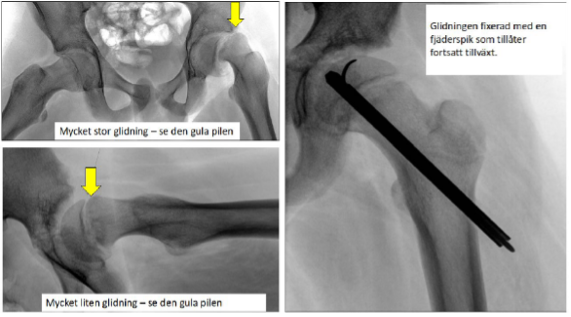

Höft, ljumsk eller knäsmärta vid belastning kan bero på cirkulationsstörning (Perthes sjukdom) eller glidning i tillväxtzonen i höftkulan (Höftfyseolys), det senare kräver akut röntgen och operation inom ett dygn.